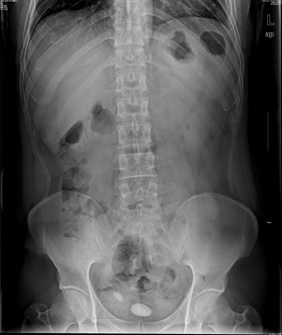

05卷-4.男,55岁,反复尿频、尿痛、排尿困难半年(本题满分2.00分)

膀胱结石

B.膀胱结石

本题答案:B

题目解析:【该题针对“X线-泌尿系结石”知识点进行考核】